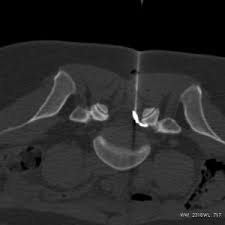

L’infiltration épidurale par voie foraminale ou inter lamaire consiste à injecter un médicament anti-inflammatoire à base de cristaux de cortisone au voisinage du nerf dont l’irradiation est responsable de votre douleur.

L’injection est effectuée soit à l’endroit où le nerf sort de la colonne vertébrale, c’est à dire dans un canal (ou foramen) situé entre deux vertèbres (voie foraminale), soit à distance du nerf (voie inter lamaire).

Le geste sera effectué par scanner. Cette technique permet de choisir le bon point d’entrée de l’aiguille et de suivre son trajet.

Pendant l’infiltration, suivez bien les recommandations du médecin et du technicien. Votre coopération est essentielle : elle contribuera à la rapidité du geste de ponction et diminuera les risques de douleur et de complications. Vous êtes installé sur le dos sur une table de scanner. Désinfection très soigneuse de la peau. Sous contrôle scanner une aiguille est mise en place à proximité du nerf. Une faible quantité de produit de contraste iodé est injectée pour vérifier la bonne position de l’extrémité de l’aiguille, puis le médicament est injecté.